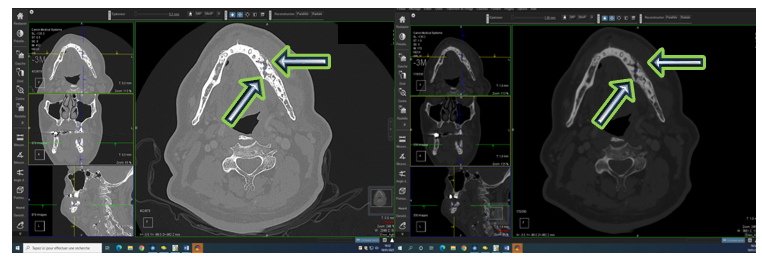

Figure 2: CT scan slice showing osteolysis of the left mandibular ramus caused by the solitary plasmacytoma.

A planning CT scan was then performed using a five-point thermoplastic mask and knee supports to ensure immobilization. Alignment was done using wall lasers positioned at the level of the tragus. The images were transferred from the treatment planning system (TPS) to the contouring console.

The planned treatment consisted of normofractionated conformational radiotherapy, with a total dose of 46 Gy delivered in 23 fractions (five sessions per week), targeting exclusively the mandibular tumor mass, without irradiation of lymph node areas.

Malignant plasma cells produce cytokines and release an osteoclast-activating factor that stimulates osteoclasts to resorb bone; consequently, on radiographic examination, they appear as well-defined osteolytic lesions with either unilocular or multilocular radiolucency (10,14). According to Lae et al., three radiographic patterns have been described in SBP: multilocular 'soap bubble' lesions, unilocular radiolucency (as seen in our patient) with a cystic appearance, and poorly defined destructive bone resorption (15). CT helps to refine the radiological image and assess the extension toward cortical and soft tissues. MRI remains a valuable imaging modality for detecting bone-involved plasmacytomas, assessing soft tissue involvement and bone marrow infiltration, and evaluating disease throughout the body. Solitary plasmacytomas show low signal intensity on T1-weighted images and high signal intensity on T2-weighted images, with homogeneous enhancement after gadolinium contrast injection (16).

In our case, there were signs of periosteal reaction with cortical destruction, potentially extending widely into the surrounding tissues.